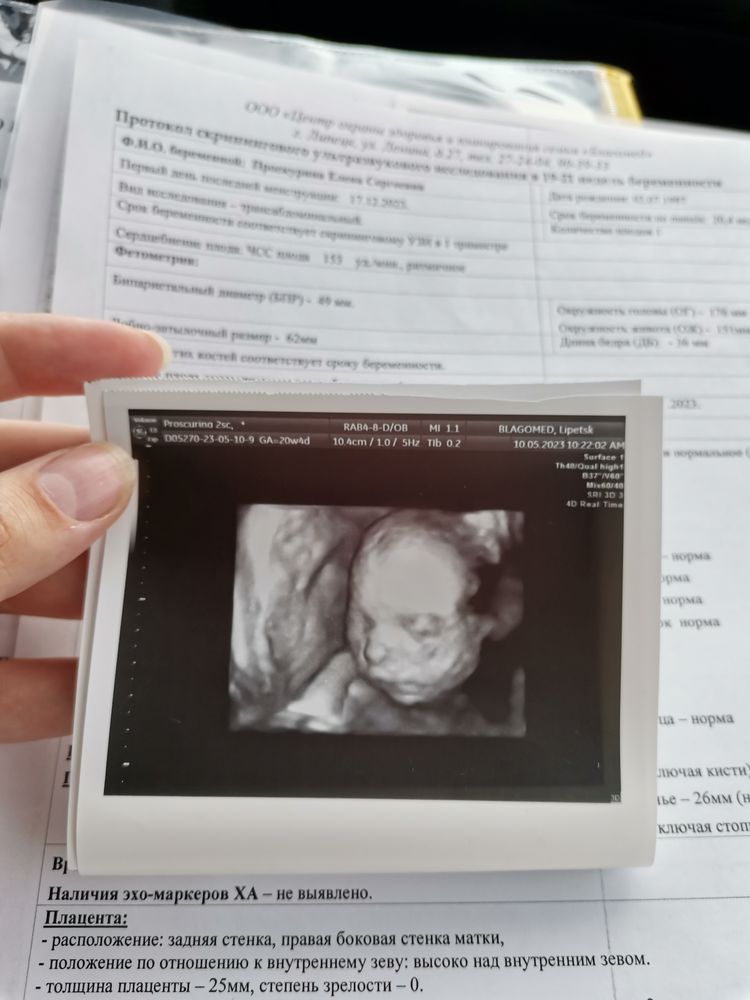

Узи. 2 скрининг❤️